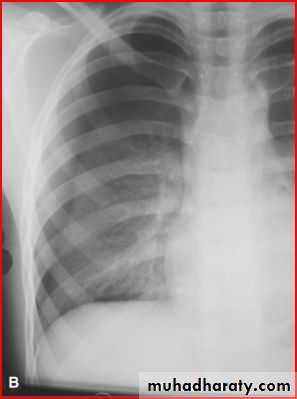

Homgenous opacity filling the rt. Hemithorax there is shefting in trachea to rt. Side mean this is collapse

Opacification of whole lt. hemithorax consolidation of pneumonea but no pleural effusion b.c there is free costophrenic angle